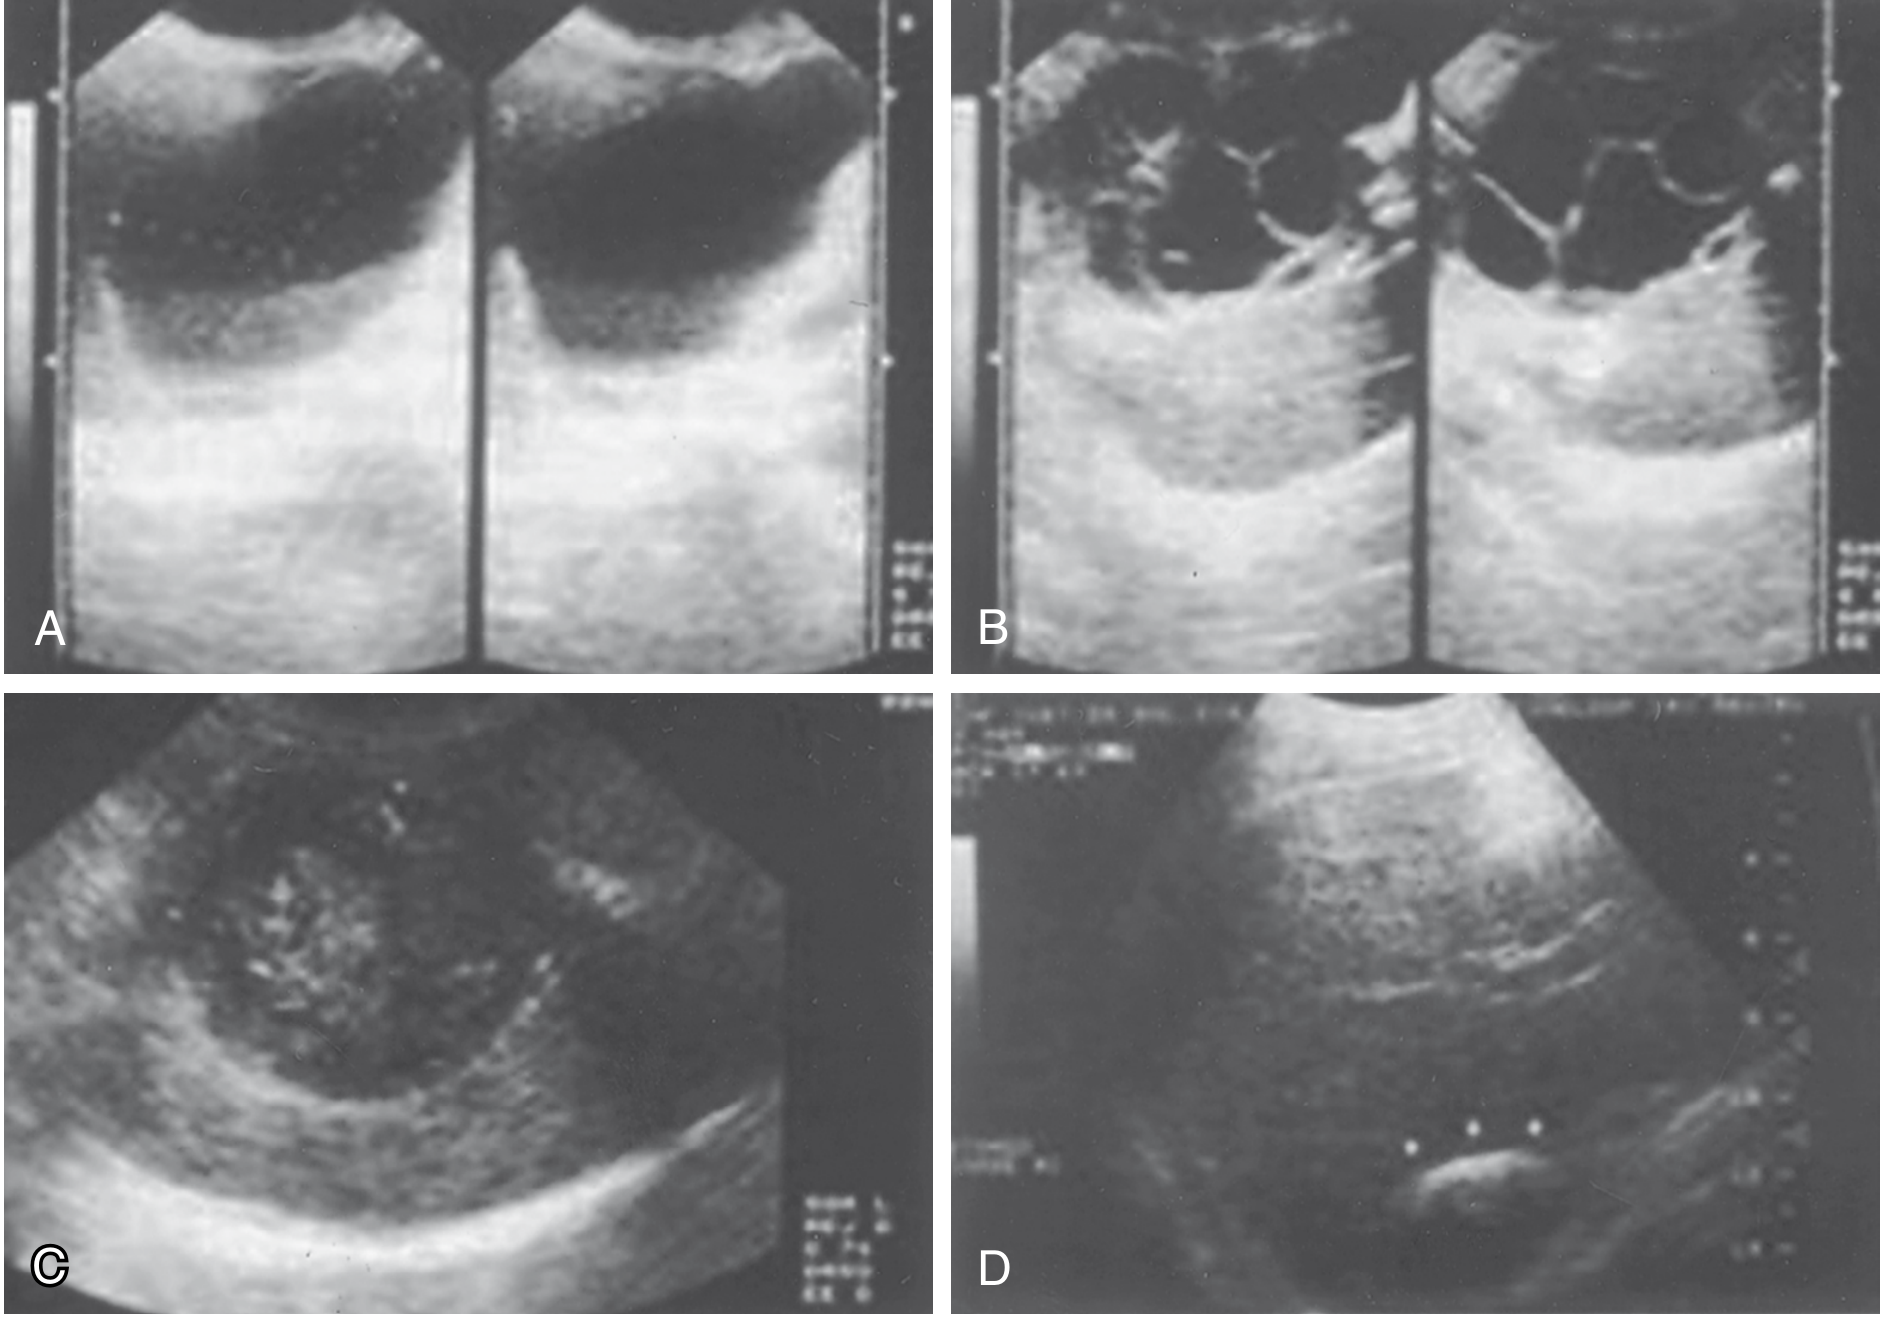

Ultrasound appearances of hydatid cyst at varying stages: (A) simple cyst with hydatid sand, (B) daughter cysts with rosette pattern, (C) amorphous solid-appearing mass, (D) calcified eggshell appearance

Fig: Ultrasound appearances — (A) Simple cyst with floating hydatid sand. (B) Daughter and granddaughter cysts, rosette sign. (C) Amorphous mass mimicking solid tumour. (D) Calcified "eggshell" wall. — Sabiston Textbook of Surgery

The WHO/Gharbi classification guides treatment choice:

WHO TypeGharbiDescription

CE1IUnilocular cyst, anechoic with hydatid sand

CE2IIIDaughter cysts, rosette pattern

CE3IIDetached/floating membrane

CE4IVHeterogeneous, degenerating

CE5VCalcified, inactive